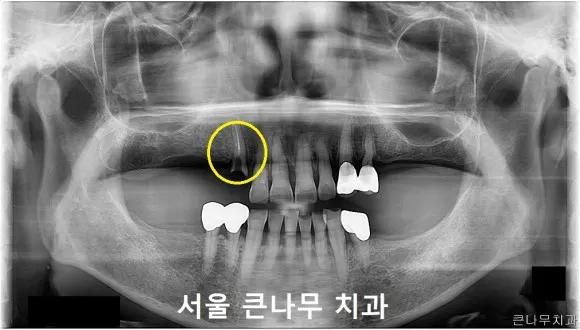

서울 큰나무 치과에 방문해 주신 70대 여성 환자의 케이스를 보겠습니다.

이 환자분의 경우, 5년 전에 위아래 모두 보험 틀니를 제작하셨지만 불편하여 잘 끼지 않는 상태셨고, 오른쪽 위에 이가 부러져 뿌리밖에 남지 않은 상태였습니다.

오른쪽 치아를 발치해 주었고, 기존에 사용하던 틀니를 이용하여 이가 빠진 부분에 인공치를 만들어주었습니다.